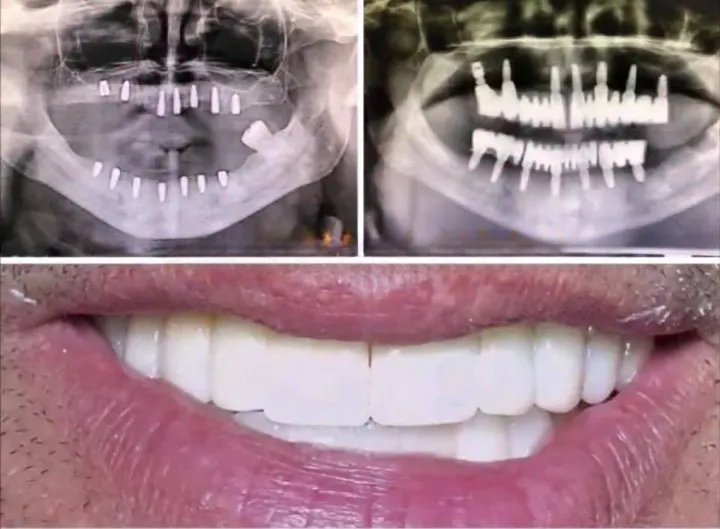

Traitement Parodontite Avancée

Thérapie non-chirurgicale et chirurgicale pour éliminer l'infection, stopper la progression du déchaussement et stabiliser les dents mobiles. Protocole personnalisé selon le stade de la maladie.